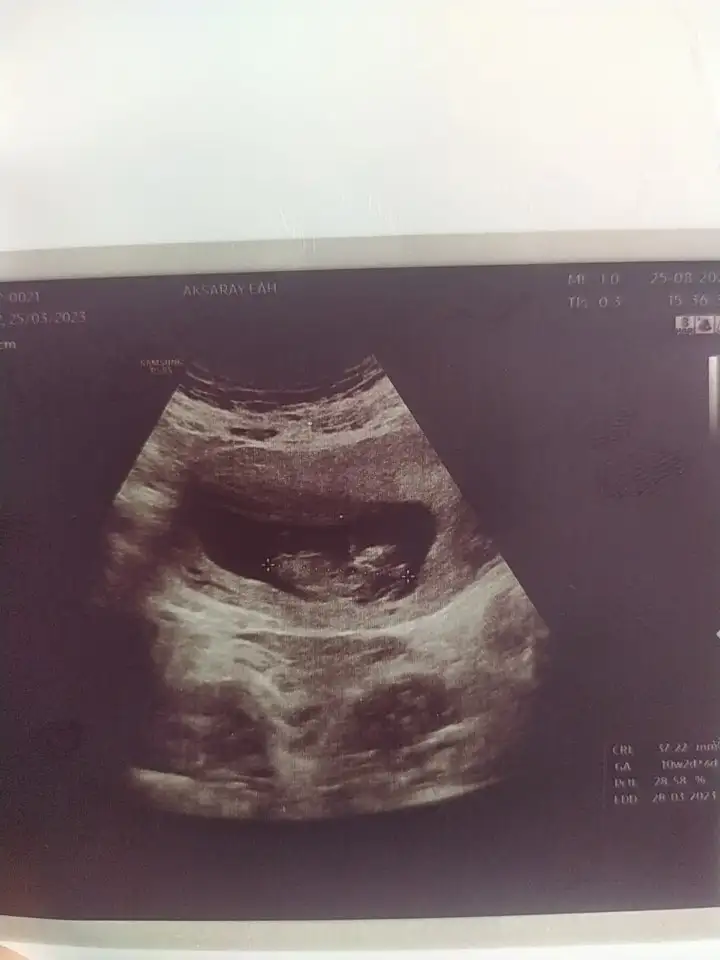

Kızlarr merhaba ☺️ Bugün doktor kontrolüm vardı covidten sonraki ilk kontrol ve çok korkuyodum çok şükür bir sorun yokmuş ☺️ Doktoruma ayağımın altında yanma var saçlarım dökülüyor dedim gebelik vitaminleri verdi ☺️ Bu sefer devletteki doktoruma gittim çok net değil sanki diğer kızların ki gibi 😅 Cinsiyet tahmini yapılabilir mi bilmiyorum 🤭 Sata göre 10+4 olması lazımdı ama 10+2 🥰